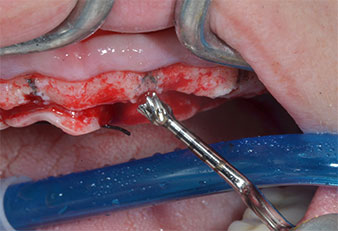

A flame-shaped, diamond-coated piezoelectric instrument (Piezomed I1) was used to mark the implant positions and to perform pilot preparation (Fig. 3). Care was taken to use an up and down movement, with reduced power, full irrigation and low pressure (below 300 g). Next a pilot instrument (Piezomed I2A/I2P) was applied for the initial 2 mm diameter enlargement of the implant sites (Fig. 4), followed by a 3 mm insert (Fig. 5).

Due to the relatively hard bone (D2) in this area, the 10 mm long implant sites at positions 11 and 21 were finalized with a 4 mm diameter rotary drill, in combination with a W&H WS-75 L surgical contra-angle handpiece, the W&H Implantmed implant motor and the optional W&H Osstell ISQ module. In contrast, due to the soft bone the posterior sites were prepared to a final 3 mm diameter using the Piezomed I3P instrument. The implants were finally placed transgingivally to osseointegrate for three months (Figs. 6-10). The existing denture was retained on four provisional implants (Fig. 8).